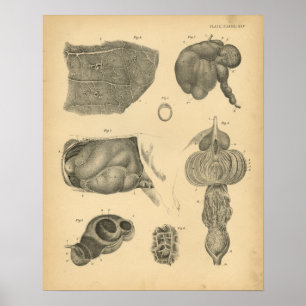

Impressão humano da anatomia dos órgãos interno

Preço15,60 €

Impressão humano da anatomia do vintage interno

Preço24,05 €

Impressão interno humano da anatomia 1841 da

Preço27,80 €